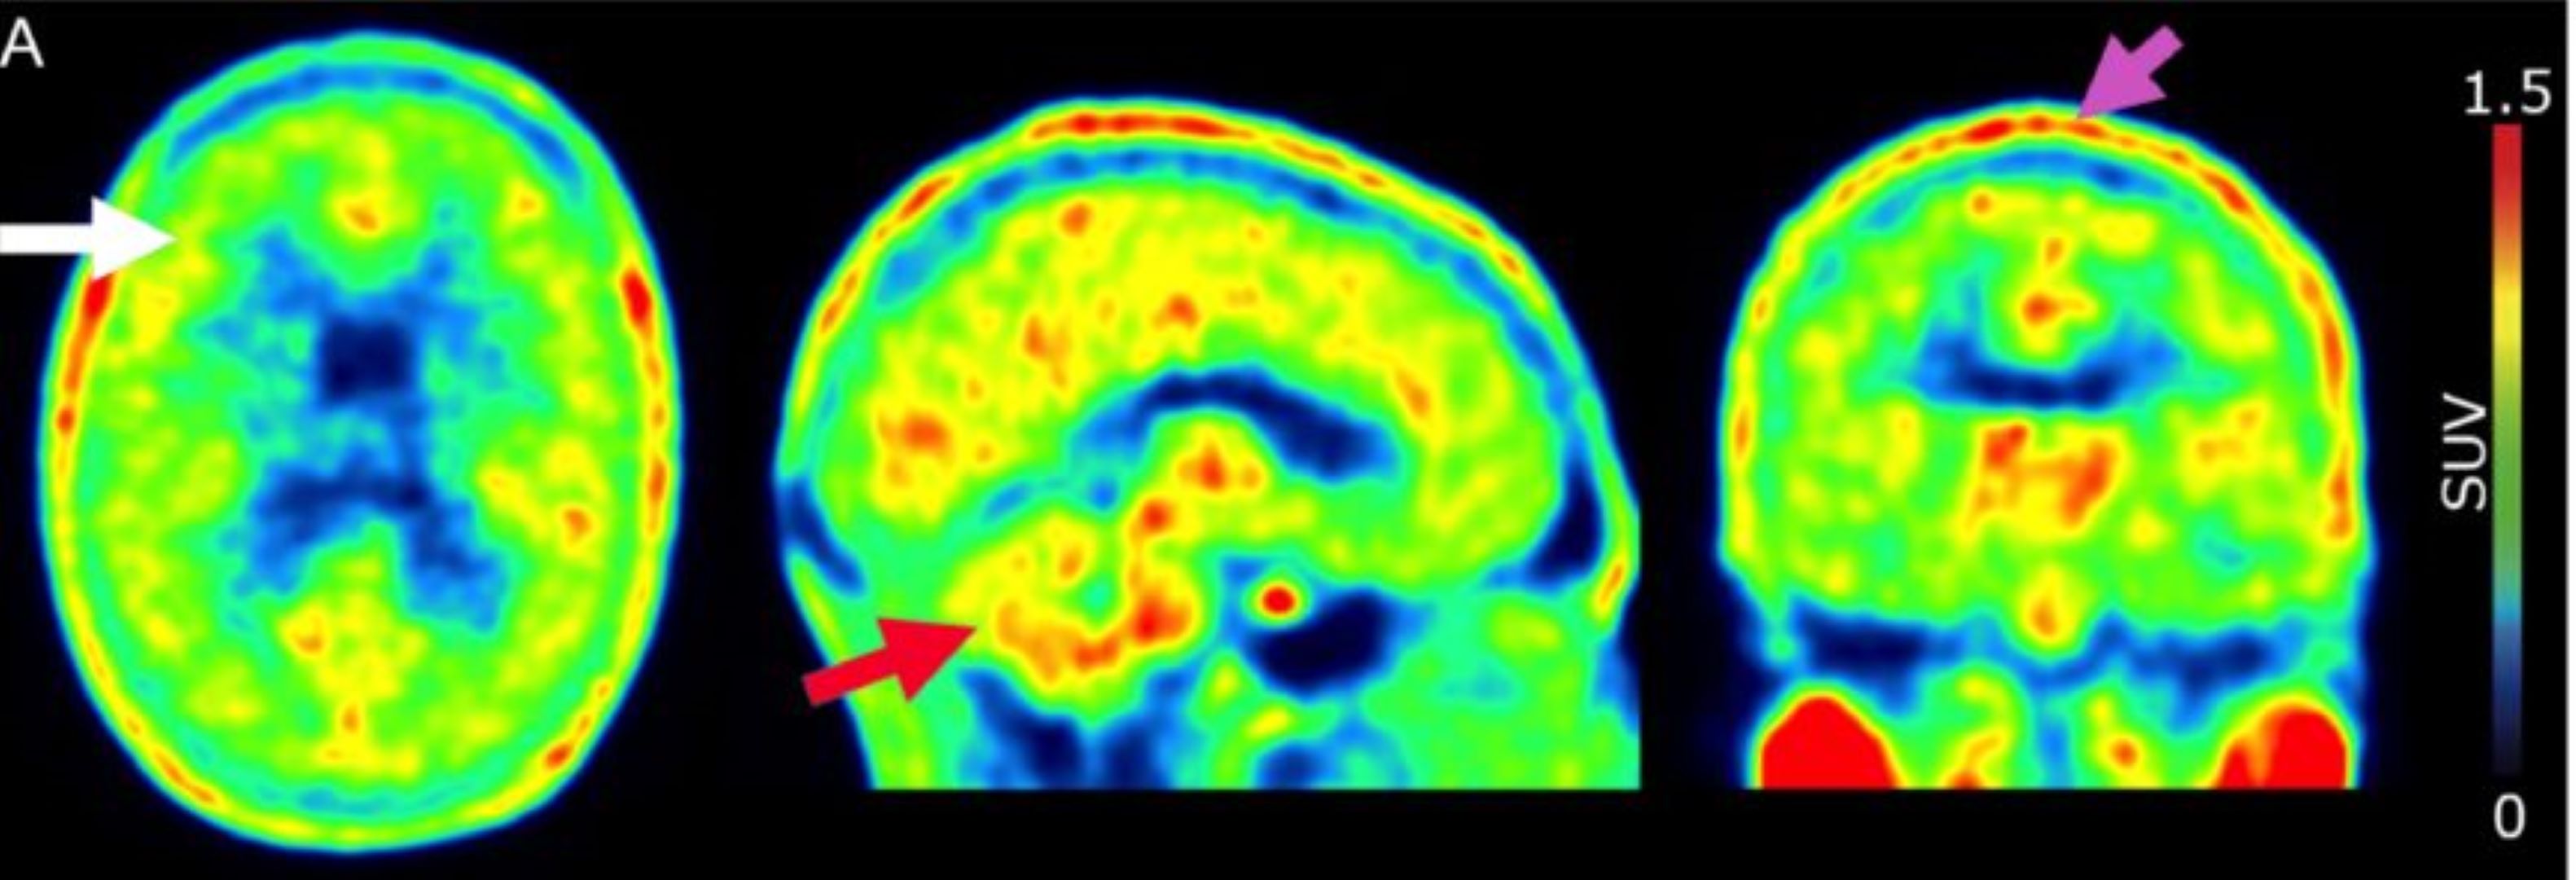

Une équipe de recherche du Département de psychiatrie et du Département diagnostique des HUG et de la Faculté de médecine de l’UNIGE, a étudié un nouveau traceur pour l’imagerie TEP pour mieux détecter l’inflammation du cerveau en ciblant la protéine TSPO, fréquente dans les maladies comme Alzheimer et la sclérose en plaques. Publiée dans Nuclear Medicine and Biology, l’étude précise sa répartition dans l’organisme et sa dosimétrie chez des volontaires en bonne santé et ouvre la voie à des outils de détection plus performants et à une médecine de précision.

Le radiopharmaceutique (ou traceur) évalué, le [18F]PBR111, est conçu pour l’imagerie TEP, aussi appelée PET scan. Il se fixe sur la protéine TSPO, dont l’expression augmente lors de neuroinflammation, ce qui permet d’approcher l’activité de cellules impliquées dans la réponse immunitaire du cerveau. Aux HUG, une partie de ces radiopharmaceutiques de recherche est produite grâce à l’Unité cyclotron, infrastructure unique en Suisse romande.

Pour établir les conditions d’utilisation en toute sécurité, les chercheuses et chercheurs ont mesuré sa répartition dans l’organisme et l’exposition liée à l’examen chez six volontaires en bonne santé, trois femmes et trois hommes, ayant reçu environ 200 MBq. Les premiers signaux sont surtout observés dans les poumons et le foie, puis l’activité s’accumule davantage dans la moelle osseuse et la vessie au fil du temps. L’exposition totale est estimée à 3.04 mSv par examen, un niveau jugé modéré pour ce type d’imagerie.

Ces données sont un prérequis pour déployer ce traceur dans des études cliniques visant à mieux caractériser l’inflammation cérébrale observée dans la maladie d’Alzheimer, la sclérose en plaques ou la sclérose latérale amyotrophique. Elles ouvrent la voie à un diagnostic et à un suivi plus précis, ainsi qu’à une médecine de précision qui mesure l’effet des traitements au plus près des mécanismes biologiques.